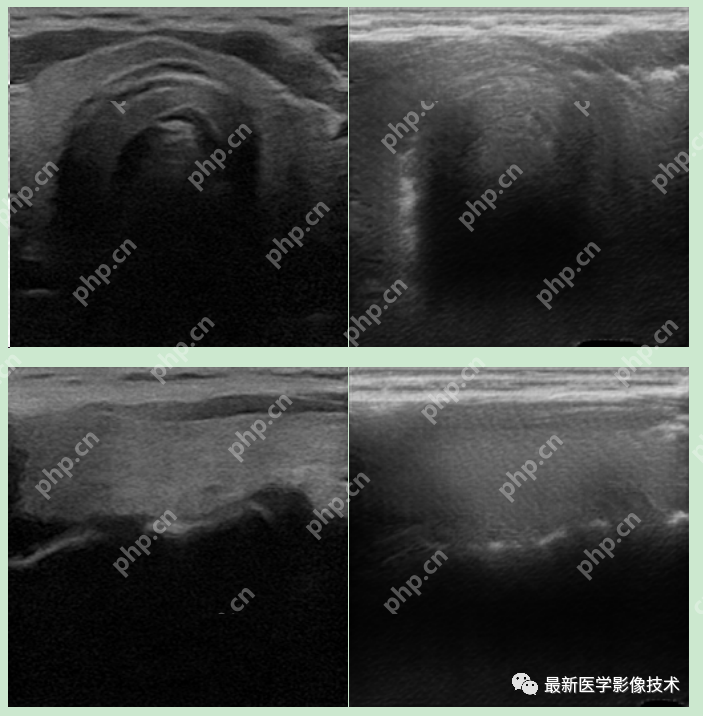

6、测试集部分生成结果

左图为低质量图像,右图为生成的高质量图像。